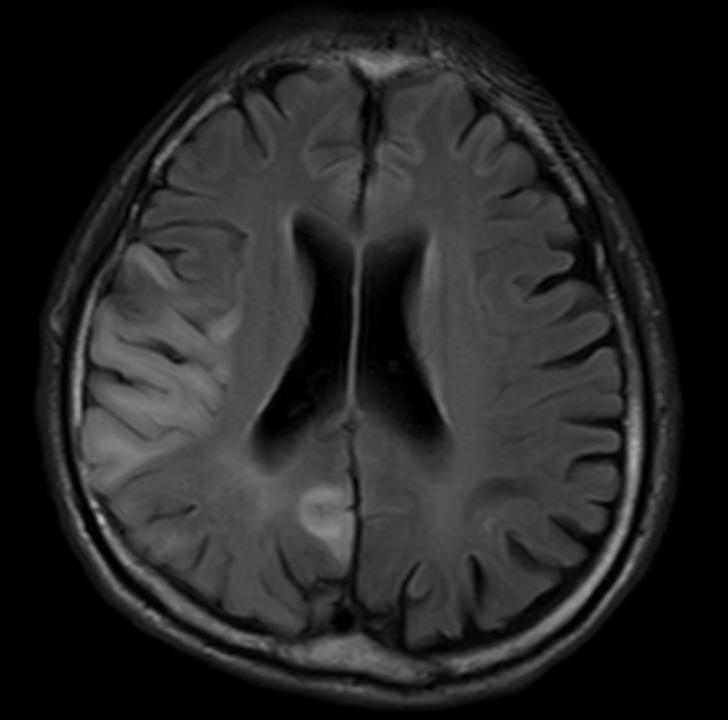

MELASはミトコンドリア病の中でも最も頻度の高い病気の一つで、低身長、全身の筋萎縮、難聴、糖尿病、頭痛、てんかん発作、乳酸アシドーシスなどいろいろな症状を呈しますが、最も特徴的な症状は反復する脳卒中様発作です(図3)。脳卒中のように突然、言葉がしゃべれなくなったり、視野の半分が見えなくなったり、手足が麻痺するなどの症状を呈します。こうした脳卒中様発作を繰り返しながら、身体機能や認知機能の障害が蓄積していきます。MELAS患者の約80%はミトコンドリアDNA(mtDNA)がコードするロイシンというアミノ酸を運搬するtRNALeu(UUR)遺伝子の一塩基変異A3243Gが原因です。この変異があるとロイシンtRNAアンチコドンのタウリン修飾が欠損し、UUGというコドンが認識されなくなり、ミトコンドリア蛋白が正常に合成できなくなります(図2)。